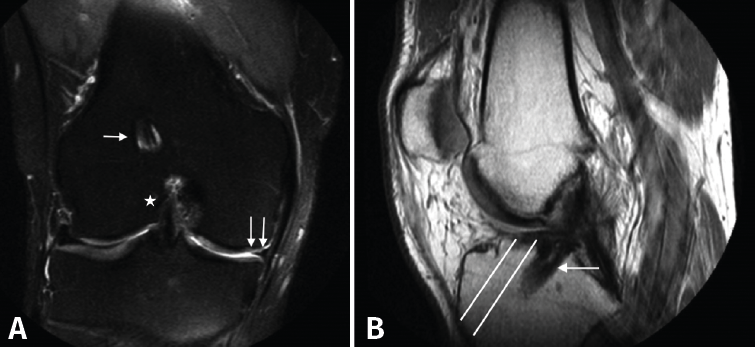

En las pruebas complementarias actualizadas presentaba, en las radiografías simples (Rx) anteroposteriores en carga de ambas rodillas (Figura 1A), un túnel femoral muy vertical, con un dispositivo de suspensión como material de fijación y algunos cambios degenerativos incipientes en el compartimento medial. En la Rx lateral de rodilla (Figura 1B) presentaba un túnel tibial muy posterior. En la resonancia magnética (RM) (Figura 2), persistía la integridad de la plastia inicial del LCA, además de los hallazgos descritos en las Rx, así como una meniscectomía amplia.

Figura 2. Resonancia magnética de la rodilla derecha. A: imagen coronal en secuencia STIR en la que se aprecian la plastia del ligamento cruzado anterior (LCA; estrella) y el túnel femoral (flecha) verticalizados, con meniscectomía medial amplia (doble flecha); B: imagen sagital en secuencia T1 en la que se aprecia el túnel tibial posterior a la situación anatómica del LCA (flecha). Líneas blancas: representación de la situación ideal del túnel tibial.